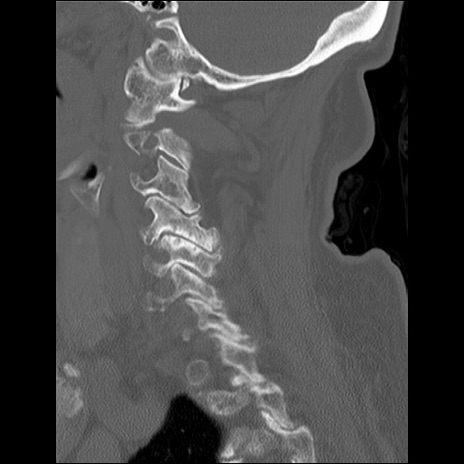

症例48 頚椎CT(矢状断像)

頚椎CT